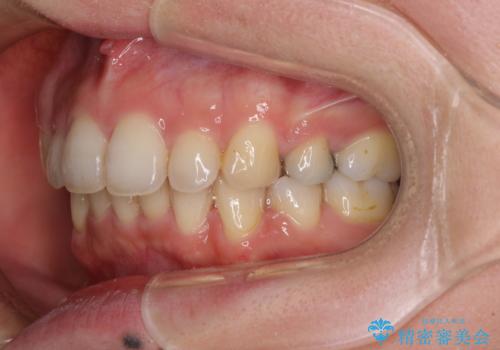

- 上下の出っ歯を気にして来院された患者様です。

口元を積極的に引っ込めるために、上下左右の第一小臼歯を4本抜歯することとしました。

元々ディープバイトのため、スペースを閉じている期間に上下前歯が接触してしまい、治療期間が想定よりも伸びてしまいました。